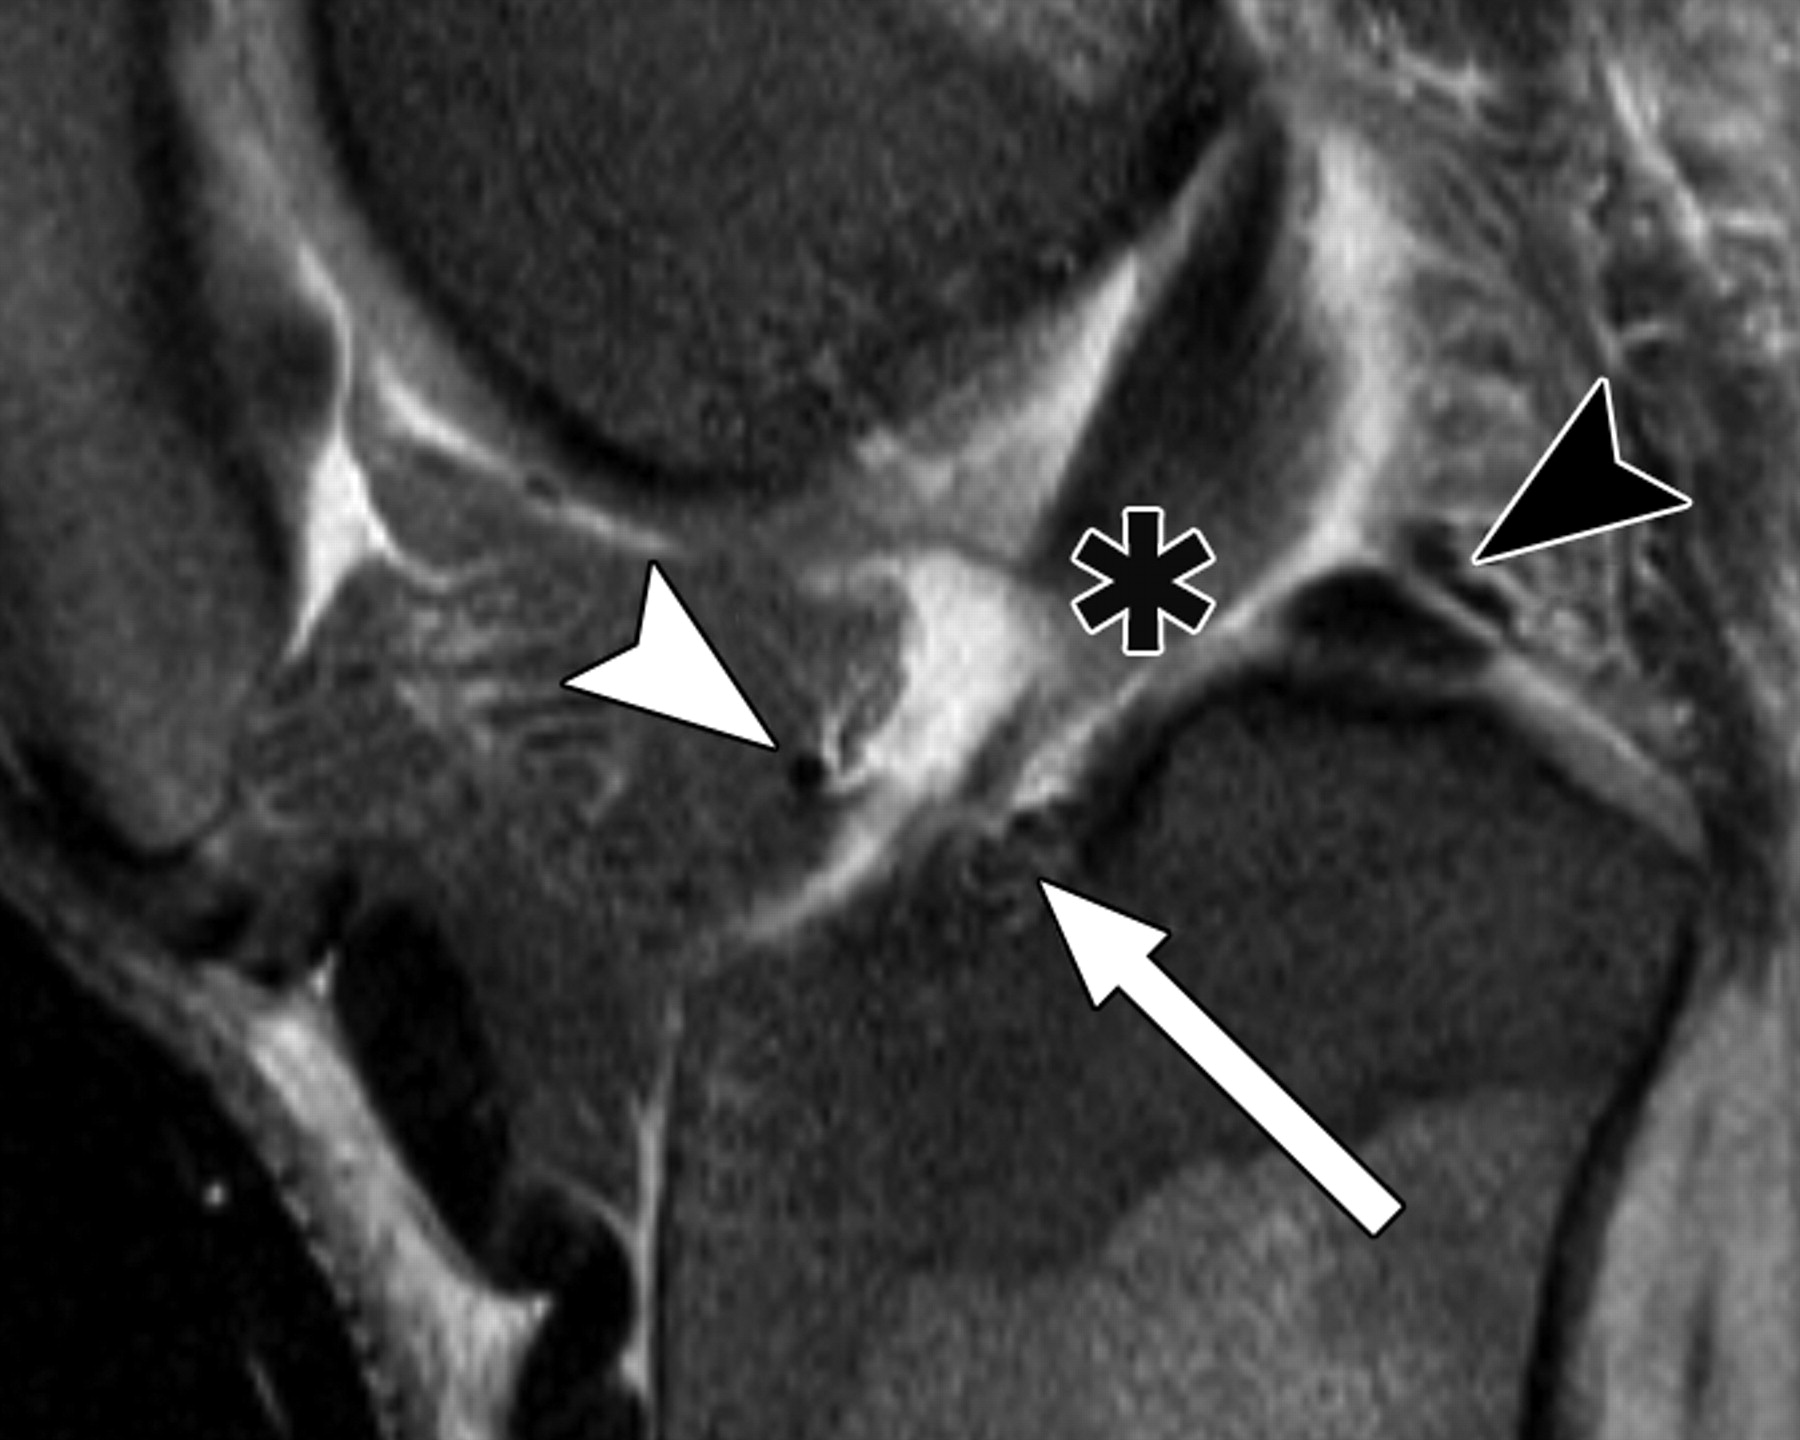

图5A-59岁男性。

中等加权、脂肪饱和、快速自旋回波(TR/TE有效值,3,700/29)3-T MR图像显示半月板后根和交叉韧带的解剖关系。

冠状面MR图像显示内侧半月板(MM)后根(箭头)覆盖后髁间区域的一个以上切片厚度。LM =外侧半月板。LT =胫骨外侧结节。

图5 B-59岁男性。中等加权、脂肪饱和、快速自旋回波(TR/TE有效值,3,700/29)3-T MR图像显示半月板后根和交叉韧带的解剖关系。

冠状面图像依次位于A的腹侧,显示外侧半月板后根(LM)(白色箭头)和内侧半月板后根(MM)(黑色箭头,B)的插入,覆盖后髁间区域的一个以上切片厚度。MT =胫骨内侧结节。

图5C-59岁男性,中等加权、脂肪饱和、快速自旋回波(TR/TE有效值,3,700/29)3-T MR图像显示半月板后根和交叉韧带的解剖关系。

图5D-59岁男性,中等加权、脂肪饱和、涡轮自旋回波(TR/TE eff,3,700/29)3-T MR图像显示半月板后根和交叉韧带的解剖关系。

通过后交叉韧带(P)的矢状图像显示内侧半月板后根的插入部位(箭头)相对于韧带插入部位位于前方。MT =胫骨内侧结节。箭头表示膝前韧带。

图5E-59岁男性,中等加权、脂肪饱和、快速自旋回波(TR/TE,3,700/29)3-T MR图像显示半月板后根和交叉韧带的解剖关系。

通过前交叉韧带(星号)的MRI图像显示外侧半月板后根的附着点(箭头)相对于内侧半月板的附着点稍靠前。圆圈表示前交叉韧带和外侧半月板前根的共同附着点。箭头表示膝前韧带。P =后交叉韧带。